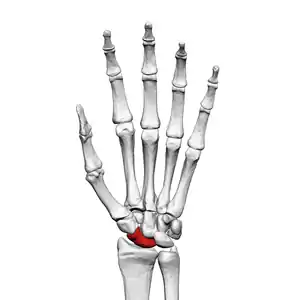

The scaphoid bone is one of the carpal bones of the wrist. It is situated between the hand and forearm on the thumb side of the wrist (also called the lateral or radial side). It forms the radial border of the carpal tunnel. The scaphoid bone is the largest bone of the proximal row of wrist bones, its long axis being from above downward, lateralward, and forward. It is approximately the size and shape of a medium cashew.

The scaphoid is situated between the proximal and distal rows of carpal bones. It is located on the radial side of the wrist, and articulates with the radius, lunate, trapezoid, trapezium and capitate.[1]:176 Over 80% of the bone is covered in articular cartilage.[2]

Scaphoid bone of the left hand (shown in red). Animation.